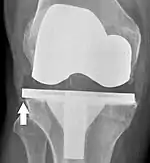

Knee replacement is routinely evaluated by X-ray, including the following measures:

- FFC: frontal femoral component angle. It is typically regarded as optimal when being 2–7° in valgus.[62]

- FTC: frontal tibial component angle, which is regarded as optimal when being at a right angle. A varus position of more than 3° has generally been found to increase the failure rate of the prosthesis.[62]

- Anterior femoral notching (the femoral component causing reduced thickness of the distal femur anteriorly), seems to cause an increased risk of fractures when exceeding about 3 mm.[63]

- LTC: lateral (or sagittal) tibial component angle, which is ideally positioned so that the tibia is 0–7° flexed compared to at a right angle with the tibial plate.[62]